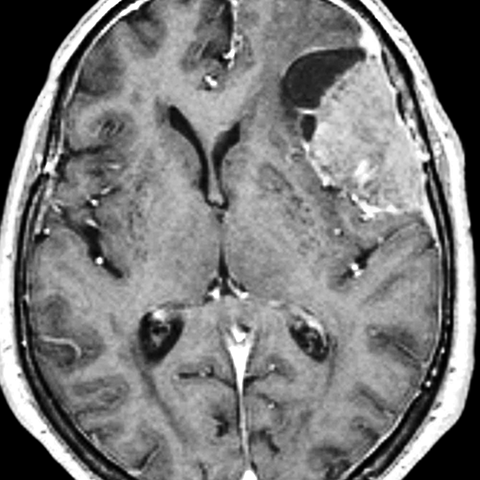

77 year old female presents with a chronic headache [2 of 2]